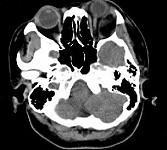

女,52岁,左眼球突出二十余年,T、T均正常,影像检查如图所示,应诊断为()A.错构瘤B.脂肪瘤C.畸胎瘤D.血管瘤E.炎性假瘤

问题 女,52岁,左眼球突出二十余年,T、T均正常,影像检查如图所示,应诊断为()

选项 A.错构瘤 B.脂肪瘤 C.畸胎瘤 D.血管瘤 E.炎性假瘤

答案 A